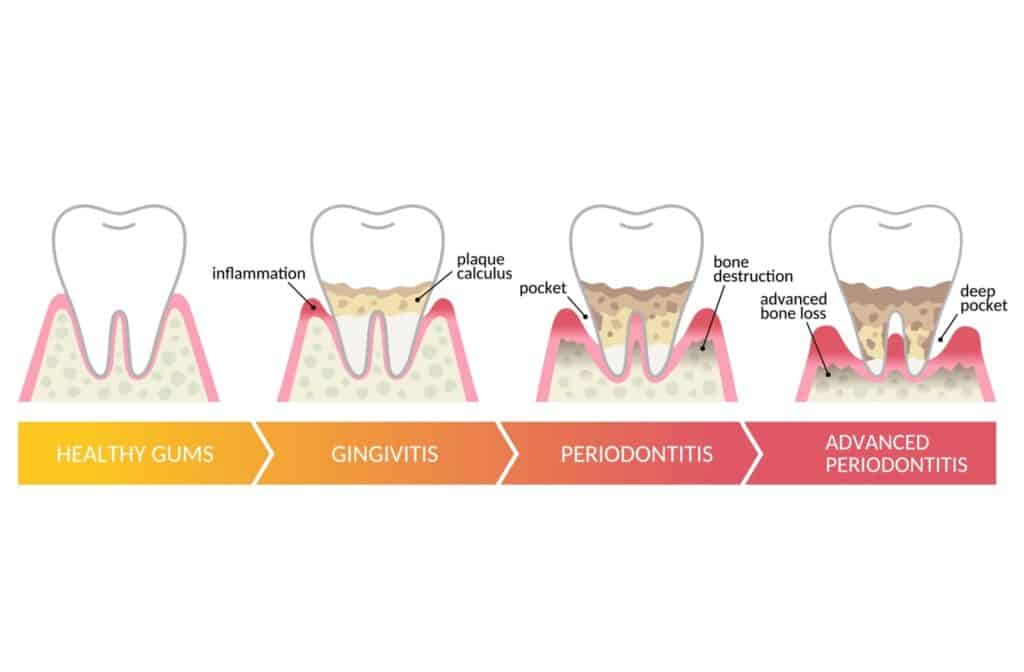

Gingivitis is the earliest form of gum disease, and bleeding during flossing is often one of the first signs. The bacteria in plaque produce toxins that cause your gums to become inflamed. At this stage, you might not feel any pain, but your gums bleed easily when you clean between your teeth.

Early gum disease is reversible with proper care and professional cleaning. However, leaving it untreated can lead to more serious problems that affect the tissues and bone supporting your teeth.